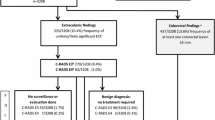

Consistency and standardization in reporting of findings at CT colonography have been aided by a reporting structure, called C-RADS, developed in 2005 [1]. This reporting structure was modeled after the successful development of Bi-RADS used in mammography. C-RADS describes how to report both individual colorectal findings and a per patient category scale summarizing all colorectal findings, ranging from C0 (incomplete/limited study) to C4 (suspected or known cancer). In addition to the colorectal scores, a similar scale of the extracolonic findings was developed, including E0 (incomplete/limited exam), E1 (normal exam or anatomic variant), E2 (clinically unimportant, no workup needed) (Fig. 1), E3 (likely unimportant, incompletely characterized, may need work-up), E4 (potentially important work-up may be needed) (Fig. 2, Table 1). The C-RADS reporting structure has become widely accepted in clinical practice. Furthermore, several studies have used the E-scores for extracolonic findings at screening CTC, which provides standardization in reporting of study results.

Most recently, USPTF in 2016 did include CT colonography in the list of accepted tests for colorectal screening, with no differences shown between modalities [6]. However, they did continue to state concerns for extracolonic findings. Specifically, the 2016 USPTF evidence report for CRC screening cited 22 original research articles (n=38,293 patients) published from 2000 to 2012 to base its discussion on the extracolonic findings at CTC [7]. These studies ranged in patient cohorts from less than 100 to over 1000 patients, including asymptomatic screening (16 studies) to higher-risk patients. Although some studies were published before or did not incorporate C-RADS, they reported prevalence across a wide range of extracolonic findings, from low clinical significance (E2) to high clinical significance (E4). As such, USPTF stated that extracolonic findings are common, occurring in 27–69% of screening tests, with 5–37% having E3 or E4 findings, 1.4–11% requiring diagnostic follow-up and 3% needing medical or surgical treatment [7]. In summary, the report concluded that extracolonic findings have the potential for both benefit and harm, with potential harms including extra costs, anxiety, and morbidity from additional diagnostic testing or treatment.

Prevalence of extracolonic findings, including cancer and aortic aneurysms

To accurately understand the prevalence of extracolonic findings is important to appreciate the clinical impact. To date, this continues to be debated and greatly misunderstood and misquoted. The prevalence of extracolonic findings varies widely with the type of patient cohort, from screening [2, 8,9,10,11,12,13,14,15,16,17,18,19,20,21,22,23,24] to diagnostic studies [25,26,27,28], and with the type of extracolonic finding, from low to high clinical significance. In symptomatic patients including colon cancer patients with metastatic disease in patient cohorts of 102–111 patients, the prevalence of extracolonic findings has ranged up to 85–89% [26, 27]. In asymptomatic screening cohorts of over 1200 patients, the prevalence of extracolonic findings with high clinical significance has been reported as low as 4.5% [2] (Table 2).

In clinical practice, the reporting of benign extracolonic findings do not lead to additional tests or patient anxiety. These E1 and E2 findings are common with no clinical consequence. These, however, can be included in studies of CT colonography, which falsely elevates prevalence of findings which in reality are dismissed clinically. On the other hand, the incidence of E3 and E4 findings have not only potential clinical significance but also can lead to extra costs due to additional imaging or treatment. As will be later discussed, it is critical, however, to understand that not all of these findings do lead to additional imaging costs, depending on their significance within the clinical context of the patient’s care or whether they represent new vs already known the disease.

An important landmark series to report the rate of E3 and E4 extracolonic findings was in an analysis of 1,410 Medicare-aged population (mean age 75) who underwent screening or surveillance CTC from 2004 to 2009 [21]. In this cohort, 196 patients (13.6%) had E3 findings. Of the patients with E3 findings, most common findings were pulmonary nodules needing follow-up in 24.7%, renal cyst or nodule in 23.4%, vascular aneurysmal atherosclerosis in 12.6%, liver lesion in 5.6%, and gallbladder or biliary abnormality in 5.6%. In addition, 41 patients (2.9%) had E4 findings, with most common findings in these patients of renal mass or cyst in 28.6%, pulmonary nodule needing follow-up in 23.8% and abdominal aortic aneurysm in 19.1%. This article helped to establish that the prevalence of extracolonic findings in Medicare-aged patients for combined E3 and E4 categories of 16.8%, far lower than the upper range of 37% stated by USPTF [7].

Larger series have more recently reported rates of extracolonic findings in average-risk screening cohorts aged 50 years and older in clinical practice. At the University of Wisconsin, the largest screening and research program of CTC in the USA, two publications reported that the combined prevalence of E3 and E4 findings in their clinical practice was 11.7% [23, 24]. This is consistent with prior studies that have reported combined rates of E3 and E4 findings to range from 11 to 16% [13, 17, 20, 22]. In the Wisconsin studies, a cohort of 7952 consecutive patients who underwent first time CTC screening examinations over an eight-year period from 2004 to 2012 were evaluated for E3 and E4 extracolonic findings. In one study, a total of 9.1% (725/7952) had E3 findings; consideration for further imaging was suggested in 84% (608/725) [24]. Of the 660 patients who were able to be followed, 8.3% (55/660) required treatment or follow-up, including eight malignancies (three renal cell carcinomas, three lymphoma, one ovarian adenocarcinoma, and one metastatic breast cancer) (Fig. 3). In the other study of the same cohort, 2.5% (202/7952) of patients had C-RADS category of E4, of which 58% (113/202) of patients underwent further imaging and 44% (89/202) had clinical follow-up [23]. A total of 180/202 were able to be followed, with 68% (123/180) proven to have clinically significant disease including 23% with a malignant or potentially malignant neoplasm and 32% with abdominal aortic or visceral artery aneurysms requiring treatment or surveillance.